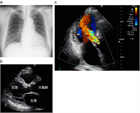

1. 聴診上胸骨左縁第3肋間で拡張期逆流性雑音を聴取し、胸部X線写真で左室拡大による左第4弓突出・心胸郭比拡大を認める患者は動脈弁閉鎖不全症(aortic regurgitationARが疑われる。経胸壁心エコー検査による診断と重症度評価が勧められる(推奨度1)